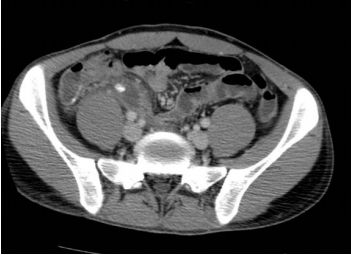

73.20歲男性因急性腹痛、高燒求診,接受對比劑注射後之電腦斷層掃描檢查如圖,最可能之診斷為何? (A)急性闌尾炎 (B)大腸憩室炎 (C)尿路結石 (D)胰臟炎